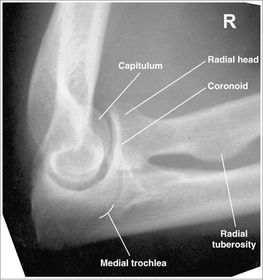

| AP Elbow | humerus is externally rotated because the epicondyles are not in profile |

| AP Oblique Elbow Internal Rotation | Insufficient obliquity |

| AP Oblique Elbow Internal Rotation | Excessive obliquity |

| AP Oblique Elbow External Rotation | forearm is not parallel to IR capitulum-radial joint is closed olecranon is not in the fossa |

| AP Oblique Elbow External Rotation | Underrotation distal forearm slightly elevated |

| AP Oblique Elbow External Rotation | Overrotation |

| Lateral Elbow | The elbow is elevated above the level of the shoulder radial head anterior to coronoid - should be superimposed capitulum too proximal to trochlea radial tuberosity seen - hand is pronated |

| Lateral Elbow | Elbow is depressed below the level of the shoulder radial head superimposed by coronoid capitulum too distal to medial trochlea |

| Lateral Elbow | the distal wrist is elevated hand is pronated because you can see the radial tuberosity - should not see that |

| AP Elbow | ANATOMY: distal humerus - proximal forearm CRITERIA: slight superimposition of proximal radius/ulna humeral epicondyles in profile open joint space POSITIONING: CR perpendicular @ midelbow |

| Medial Oblique Elbow | ANATOMY: proximal radius/ulna, distal humerus, medial epicondyle and trochlea CRITERIA: coronoid process in profile radial head and neck should superimpose the ulna olecranon process seen within olecranon fossa POSITIONING: CR perpendicular @ midelbow |

| Lateral Oblique Elbow | ANATOMY: open joint space, radial head, neck, tuberosity, and capitulum CRITERIA: radial head, neck, and tuberosity are free of superimposition humeral epicondyles and capitulum in profile POSITIONING: CR perpendicular @ midelbow |

| Lateral Elbow Evaluation Criteria | ANATOMY: distal humerus, proximal forearm, entire elbow joint CRITERIA: humeral epicondyles are superimposed radial tuberosity is invisible (if visible the hand is pronated) half of the radial head superimposed by coronoid process Elbow is flexed 90 degrees to see/not see fad pads 3 concentric arcs visible POSITIONING: CR perpendicular @ lateral epicondyle |